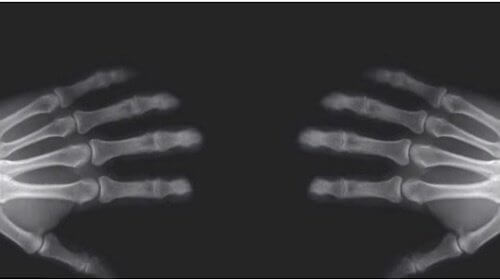

Lederna är de områden där benen möts. Alla leder har en del som kallas ledkapsel, som skyddar lederna och innehåller ett naturligt smörjmedel som kallas ledvätska. Det behövs för att lederna ska kunna röra sig ordentligt. Denna vätska är vad som gör att vi kan knäcka med fingrarna, då ledkapslarna innehåller gasbubblor som orsakar det karaktäristiska ljudet.

Detta var en upptäckt som gjordes av forskare i Kanada, och till hjälp hade man en magnetröntgenkamera.